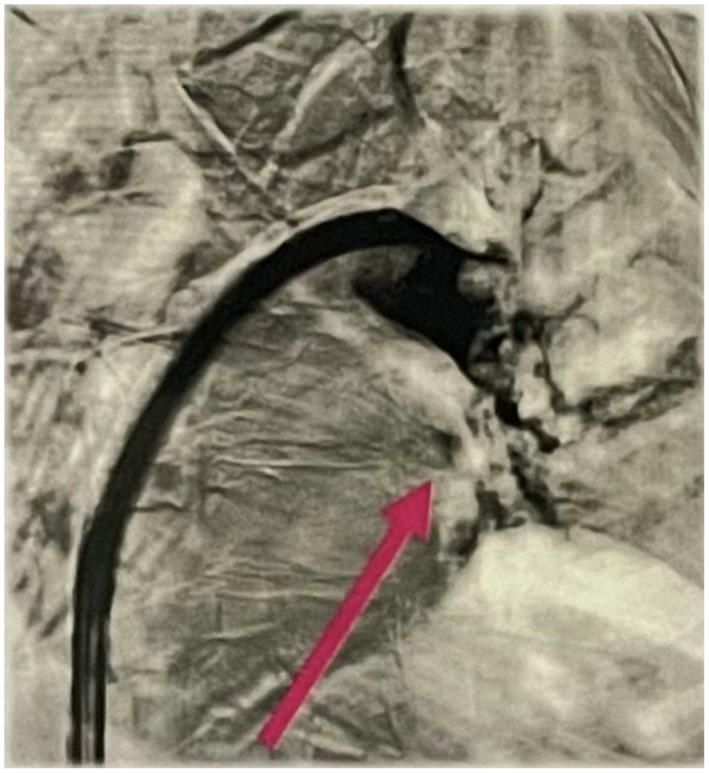

This case report discusses the effectiveness of the Inari FlowTriever system in treating a right atrial (RA) clot in-transit in a 55-year-old male patient with Becker's muscular dystrophy (BMD). BMD is an X-linked recessive muscle disease caused by mutations in the gene that code for the protein dystrophin, which is associated with partially functional dystrophin in variable amounts. Right heart thrombi (RHT) are thrombi that can be visualized in the right atrium, right ventricle, or proximal surrounding vasculature. The Inari FlowTriever system was used to treat RA clot in-transit and removed acute, subacute, and chronic clot in a single session without the use of thrombolytics and subsequent ICU stay. The estimated blood loss with the FlowSaver system was approximately 150 mL. This report complements the FLARE study by highlighting the effectiveness of the FlowTriever system for mechanical thrombectomy of RA clot-in-transit in a patient with BMD.

本病例报告讨论了Inari FlowTriever系统在治疗一名患有贝克肌肉营养不良症(BMD)的55岁男性患者右心房(RA)移动性血栓方面的有效性。BMD是一种X连锁隐性肌肉疾病,由编码抗肌萎缩蛋白的基因突变引起,该蛋白与数量不等的部分功能性抗肌萎缩蛋白相关。右心血栓(RHT)是指可在右心房、右心室或近端周围血管系统中显影的血栓。Inari FlowTriever系统用于治疗移动性RA血栓,在不使用溶栓药物且无需后续入住重症监护病房的情况下,单次治疗即可清除急性、亚急性和慢性血栓。使用FlowSaver系统的估计失血量约为150毫升。本报告通过强调FlowTriever系统对BMD患者移动性RA血栓进行机械血栓切除术的有效性,对FLARE研究进行了补充。